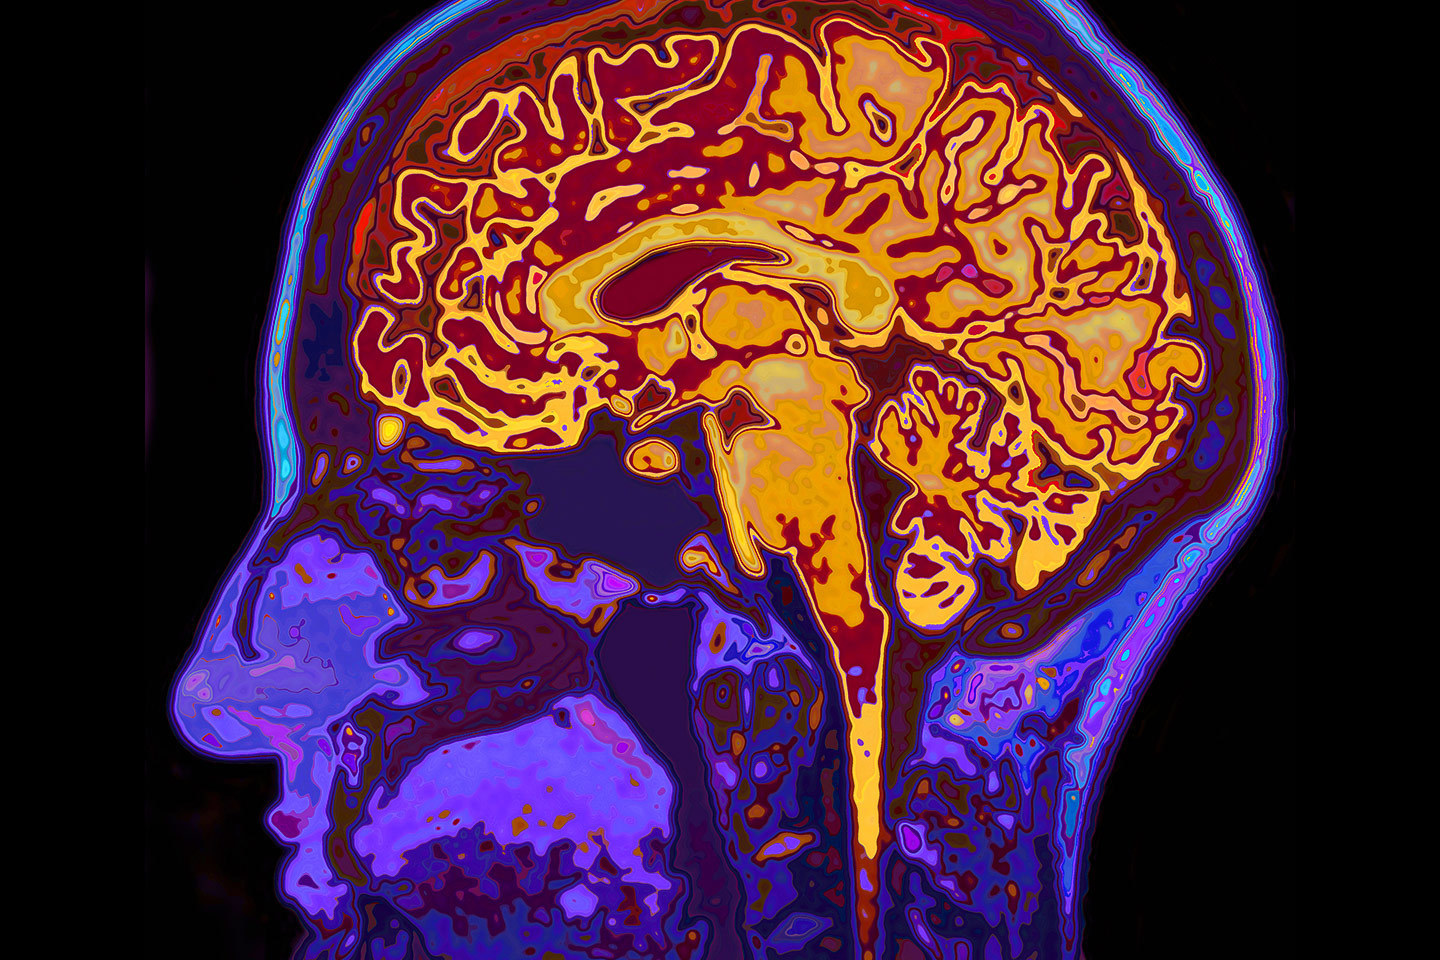

People with delirium — a sudden decline in awareness, attention and thinking — are 12 times more likely to develop dementia. And because there is no cure for Alzheimer’s and related dementias, prevention is key.

“Clinicians have known for a long time that minor medical conditions and surgical procedures can tip older individuals with mild cognitive impairment into a state of severe and sudden delirium,” Paydarfar said. “We are interested in detecting and reversing delirium early because we hypothesize that delirium is a neurotoxic state that damages neurons and accelerates brain degeneration leading to dementia. This important scientific and clinical question may be relevant to understanding the cause and treatment of Alzheimer’s disease and other neurodegenerative disorders.”